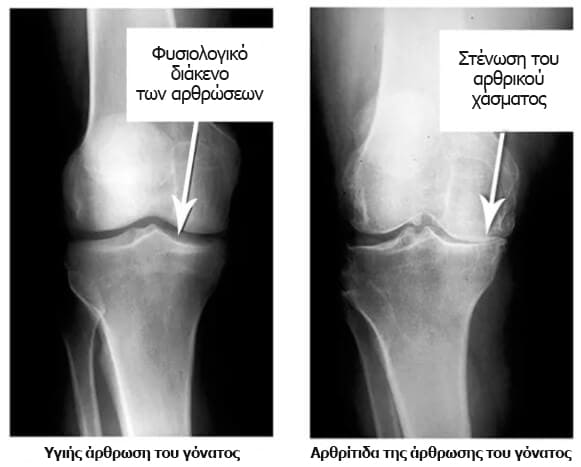

Κοιτάξτε αυτές τις εικόνες ακτίνων Χ, μπορείτε να δείτε ότι δεν υπάρχει αρθρική κοιλότητα στη δεξιά ακτινογραφία, τα οστά τρίβονται μεταξύ τους, προκαλώντας έντονο πόνο. Είναι πολύ δύσκολο να σταματήσεις αυτή τη διαδικασία!